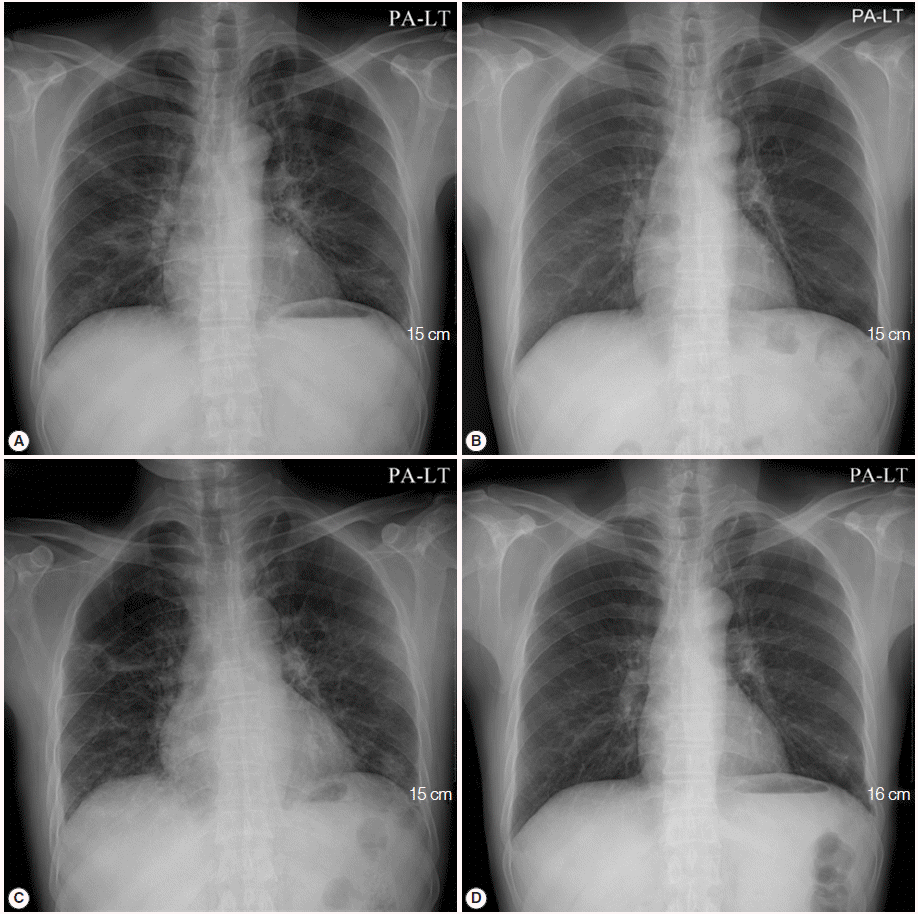

A 50-year-old male visited the outpatient clinic and complained of fever, poor oral intake, and weight loss (6 kg loss in 2 months). Routine laboratory tests and a chest X-ray were performed. Complete blood counts revealed mild leucopenia (WBC 3,720/μl), mild anemia (Hb 11.2 g/dl), and mild eosinophilia (830/μl), however, a normal platelet level (246,000/μ) was observed. Liver function tests showed elevated liver enzymes (AST 61 IU/L, ALT 74 IU/L, and GGT 215 IU/L), and serologic studies for hepatitis B virus, hepatitis C virus, human immunodeficiency virus (HIV), and syphilis were negative. A routine chest X-ray yielded streaky and fibrotic lesions in both lungs (Fig. 1A), which led to further evaluation using contrast chest computed tomography (CT). The chest CT revealed multifocal peribronchial patchy ground-glass opacities in both lungs with septated cystic lesions in the left upper lobe, and the right lower lobe (Fig. 2A, B).

Bronchoscopy was performed, but no endobronchial lesions were observed. Bronchoalveolar lavage (BAL) was performed in the right middle lobe. Cell counts in BAL revealed a lymphocyte-dominant leukocytosis (white cells 342/μl, neutrophils 9%, lymphocytes 37%, eosinophils 5%, and macrophages 49%). Further analysis of lymphocyte subsets showed a predominance of cytotoxic T cells (cytotoxic T cells 98.3%, T helper cells 1.7%, natural killer cells 3%, and B cells 0.1%). Cytologic studies, acid-fast bacillus stain, and PCR for tuberculosis and non-tuberculotic mycobacteria in the BAL fluid exhibited negative results. A tuberculin skin test and interferon-γ release assay (Quantiferon®; Carnegie, Victoria, Australia) were also negative. A video-assisted wedge resection of the left upper lobe was performed. Upon histological examination, hematoxylin and eosin (H&E) staining revealed eosinophilic frothy exudates in alveolar spaces accompanied by mild interstitial inflammation, and Grocott-Gomori’s methenamine silver (GMS) stains, performed during the histological examination, revealed many cystic- and trophic-form organisms (arrows) in the alveolar exudate, consistent with P. jirovecii infection (Fig. 3). Trimethoprim-sulfamethoxazole (TMP-SMX) was administered orally (2 double strength TMP-SMX tablets every 8 hr) [11]. The patient’s fever subsided within 3 days (from 38.5˚C to 37.0˚C), and the streaky and fibrotic lesions observed in both lungs on the chest X-ray were also markedly improved (Fig. 1B) after 12 days of TMP-SMX administration, which enabled the patient to be discharged.

TMP-SMX treatment continued to be administrated for additional 17 days following the patient’s discharge from the hospital. However, the patient complained of cough again, and a follow-up chest X-ray showed aggravation of the streaky and fibrotic lesions in both lungs (Fig. 1C). The patient was readmitted to the hospital, and chest CT was rechecked. A follow-up chest CT revealed an aggravation of multifocal peribronchial ground-glass opacity and septated cystic lesions in both upper lungs, and a newly appeared consolidation in the left lower lobe (Fig. 2C, D). P. jirovecii was clinically suspected to be resistant to TMP-SMX, and molecular studies carried out using PCR with primers Dp15 (5´-TCTGAATTTTATAAAGCGCCTACAC-3´) and Dp800 (5´-ATTTCATAAACATCATGAACCCG-3´) demonstrated mutations at codons 55 and 57 of the dihydropteroate synthase (DHPS) gene as a previous report [12].

Primaquine (4 mg/kg/day intravenous once daily) and clindamycin (600 mg intravenous every 8 hr) were administrated for 3 weeks in place of the TMP-SMX. Consequently, the cough was resolved, and a follow-up chest X-ray showed improvement of the streaky and fibrotic lesions in both lungs (Fig. 1D). We strongly suspected that HIV infection was an underlying condition, and rechecked the HIV immunoassay, which was determined to be positive. Further evaluation of HIV infection was performed; the titer of HCV RNA was determined to be 110,000 copies/ml, and the number of T helper cells in the peripheral blood was only 3/μl. Antiviral treatment regimen targeting the HIV was initiated, including lopinavir (800 mg/day), ritonavir (200 mg/day), lamivudine (300 mg/day), and zidovudine (600 mg/day), and the patient was discharged.